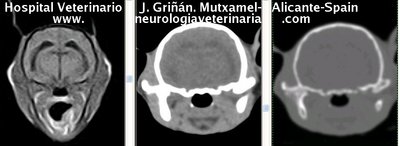

Se muestran cortes transversales de Resonancia Magnética (imagen a la izqda del lector), TC contrastado para tejidos blandos (imagen del centro) y TC contrastado para tejidos duros (imagen de la derecha del lector).

Nótese como la Resonancia supera al TC en el contraste de tejidos blandos (encéfalo y médula espinal) y en el de líquidos (ojo y líquido cefalorraquídeo), mientras que el TC supera a la resonancia en el contraste de tejidos duros (hueso) y aire (senos, cavidad nasal y bullas)

Cortes a nivel de los lóbulos cerebrales parietales